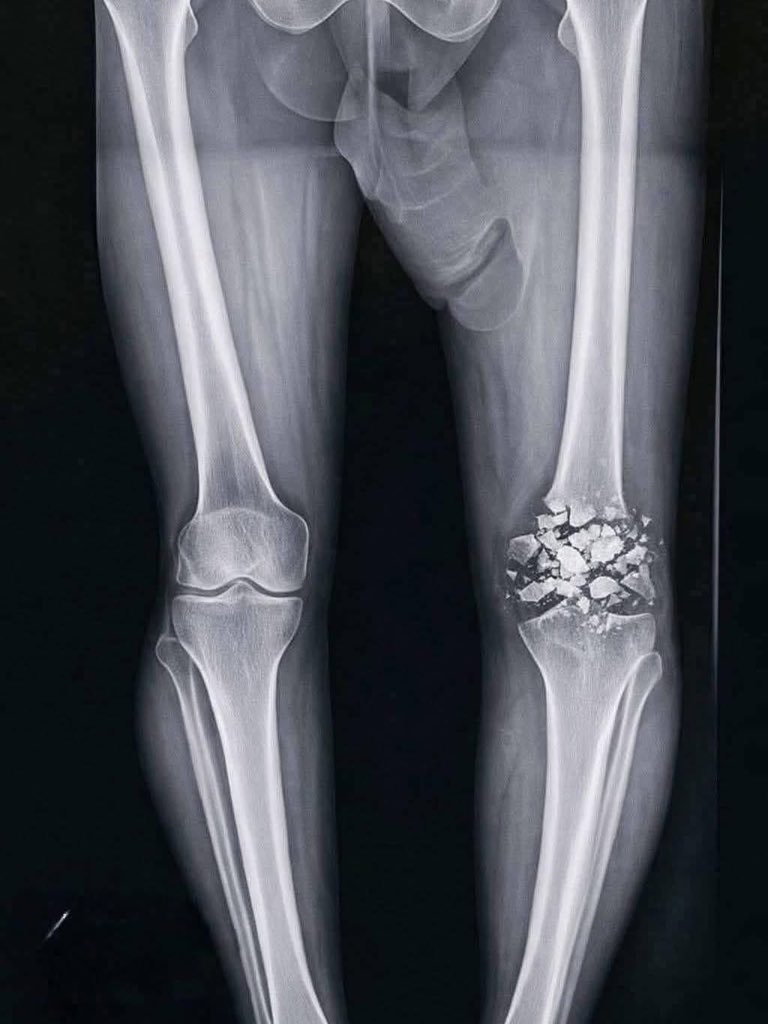

粉砕骨折ってどうやって治すの

こっから膝の骨復元できる気がしない…

おそらく人工関節になると思うがそれにしてもでっか

膝はまぁ無理だけどもなんか別に素材で置き換えるとか出来なかったっけ

AIで生成したような見事な粉砕所帯だ

昔は漫画の粉砕骨折にへー位の気持ちでいたけど冷静に考えると絶対元に戻らんよなこれ

TKAするよりも小骨片を全部取り除く方が遥かに面倒くさそう

ここまで割れると後遺症もでてくるのかな